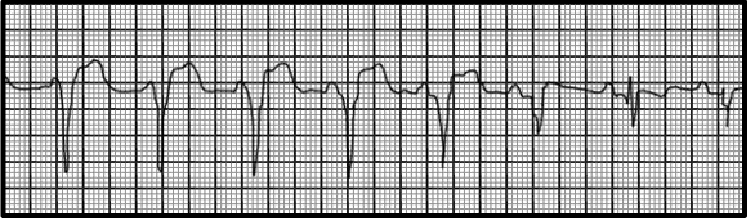

You are incorrect - the best interpretation of the rhythm strip in our patient is non-sustained ventricular tachycardia.

Your choice: Accelerated idioventricular rhythm

This rhythm strip shows accelerated idioventricular rhythm. The characteristic features demonstrated here include an episode of wide, regular QRS complexes at a rate greater than sixty, but less than one hundred beats per minute that are unrelated to any P wave . The configuration of these QRS complexes is different than the sinus QRS .